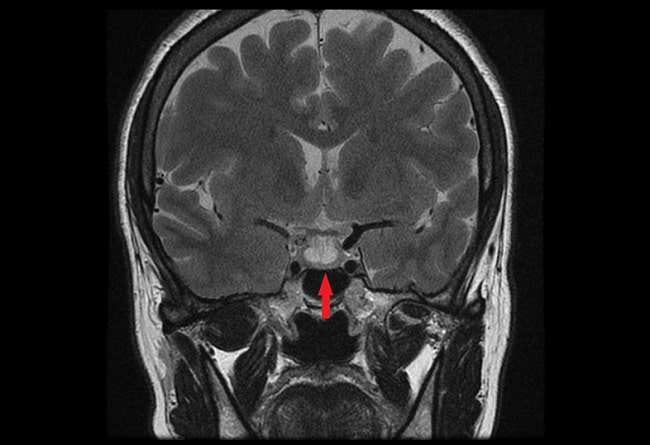

Wanita yang mengalami remisi memiliki ukuran tumor yang lebih kecil saat sebelum hamil. Tidak terdapat perbedaan tingkat remisi yang signifikan antara tipe mikroprolaktinoma dengan makroprolaktinoma. Setelah pemeriksaan MRI pertama yang dilakukan untuk pemantauan, terdapat penurunan ukuran tumor pada 23% wanita yang hamil, dan 39% pada wanita yang menyusui.[11]

Dalam sebuah kohort retrospektif di India yang melibatkan 25 wanita dengan 31 kehamilan, dilaporkan terdapat 41,6% remisi hiperprolaktinemia yang diinduksi kehamilan. Kemungkinan remisi lebih tinggi didapatkan pada pasien dengan durasi pengobatan agonis dopamin sebelum kehamilan yang lebih panjang, ukuran adenoma pra-kehamilan yang kecil, dan kadar prolaktin awal yang lebih rendah. Dalam studi ini, remisi diperiksa menggunakan MRI pada kunjungan post partum terakhir dan kadar prolaktin serum.[13]

Prolaktinoma merupakan tumor yang sering terjadi pada wanita usia subur. Beberapa bukti ilmiah menunjukkan bahwa kehamilan dan menyusui dapat menginduksi remisi dari prolaktinoma. Remisi dapat diperiksa dengan melihat ukuran tumor melalui MRI dan kadar prolaktin serum. Faktor yang meningkatkan kemungkinan remisi adalah durasi terapi dengan agonis dopamin sebelum kehamilan, ukuran prolaktinoma yang lebih kecil, serta kadar prolaktin baseline yang lebih rendah.